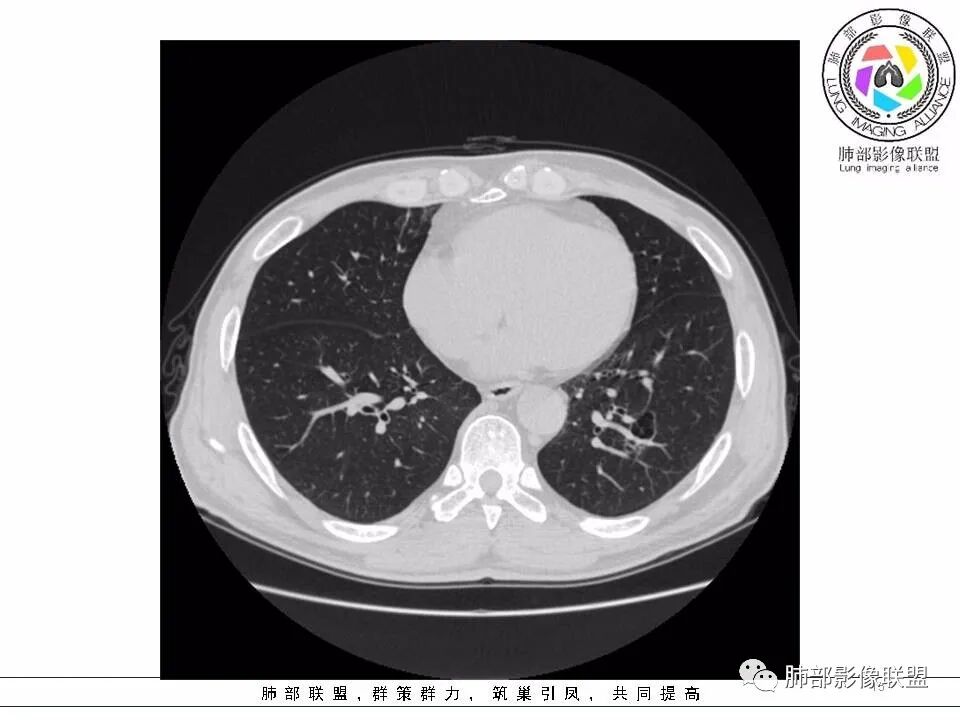

左下肺囊性病变,边界不规则,有磨玻璃,内分隔,壁厚薄不均,内有壁结节,考虑囊腔样腺癌。

男性,发热,肿瘤标志物不高,影像:左下肺类圆形囊腔,内有丝丝缕缕,周边有渗出,右肺少许条索,第一印象:囊腔型腺癌

老年男性,左肺下叶囊腔,与临近支气管关系紧密,壁厚薄不均,周围可见实性成分,腔内密度不均匀,可见索条及结节,考虑囊腔型肺癌

男性患者,左肺下叶囊性病变,壁厚薄不均,部分壁较厚,周围可见磨玻璃影,考虑周围型肺癌,腺癌可能。

53岁男性,左肺囊腔性病变,边界不规则,局部有磨玻璃和短毛刺,内见分隔(血管穿行?)、壁薄厚不均局部有结节,可见支气管进入并狭窄,考虑囊腔样腺癌。

53岁男性,间断发热半月余。CT:左下肺囊腔样病变,内见分隔及点状线条样影,未见壁结节,与支气管关系不清楚(待重建进一步观察),局部边缘见边界尚清楚的磨玻璃影。考虑囊腔型肺癌(腺癌)可能性大。

53岁男性,间断发热半月余,肿瘤指标不高。CT:左下肺囊腔样病变,内见分隔及点状线条样影,壁偏心性增厚,下缘血管穿过并增粗,后方伴边缘清晰,磨玻璃影,边缘有轻度膨隆及分叶,支气管未见截断。考虑囊腔型腺癌可能性大。

53岁男性,间断发热半月。胸CT:左下叶囊腔性病变,外形边界不规则,周围有边界较清楚磨玻璃,囊内见分隔,囊壁厚薄不均,壁结节,内有小囊,血管集束。考虑:囊腔样腺癌?鉴别:肺大疱、CPAM、PLCH等。

2.左肺下叶外基底段囊腔样病灶,轮廓柔和,壁厚薄不均,见壁结节。内见分隔或脊状突起。腔内见血管穿行。

3.囊壁外环以磨玻璃影,边界较清楚。

1.囊腔壁厚薄不均,壁结节,内有分隔,其内有血管穿行,指向新生物。

2.临近有边界清楚磨玻璃影,指向腺癌。